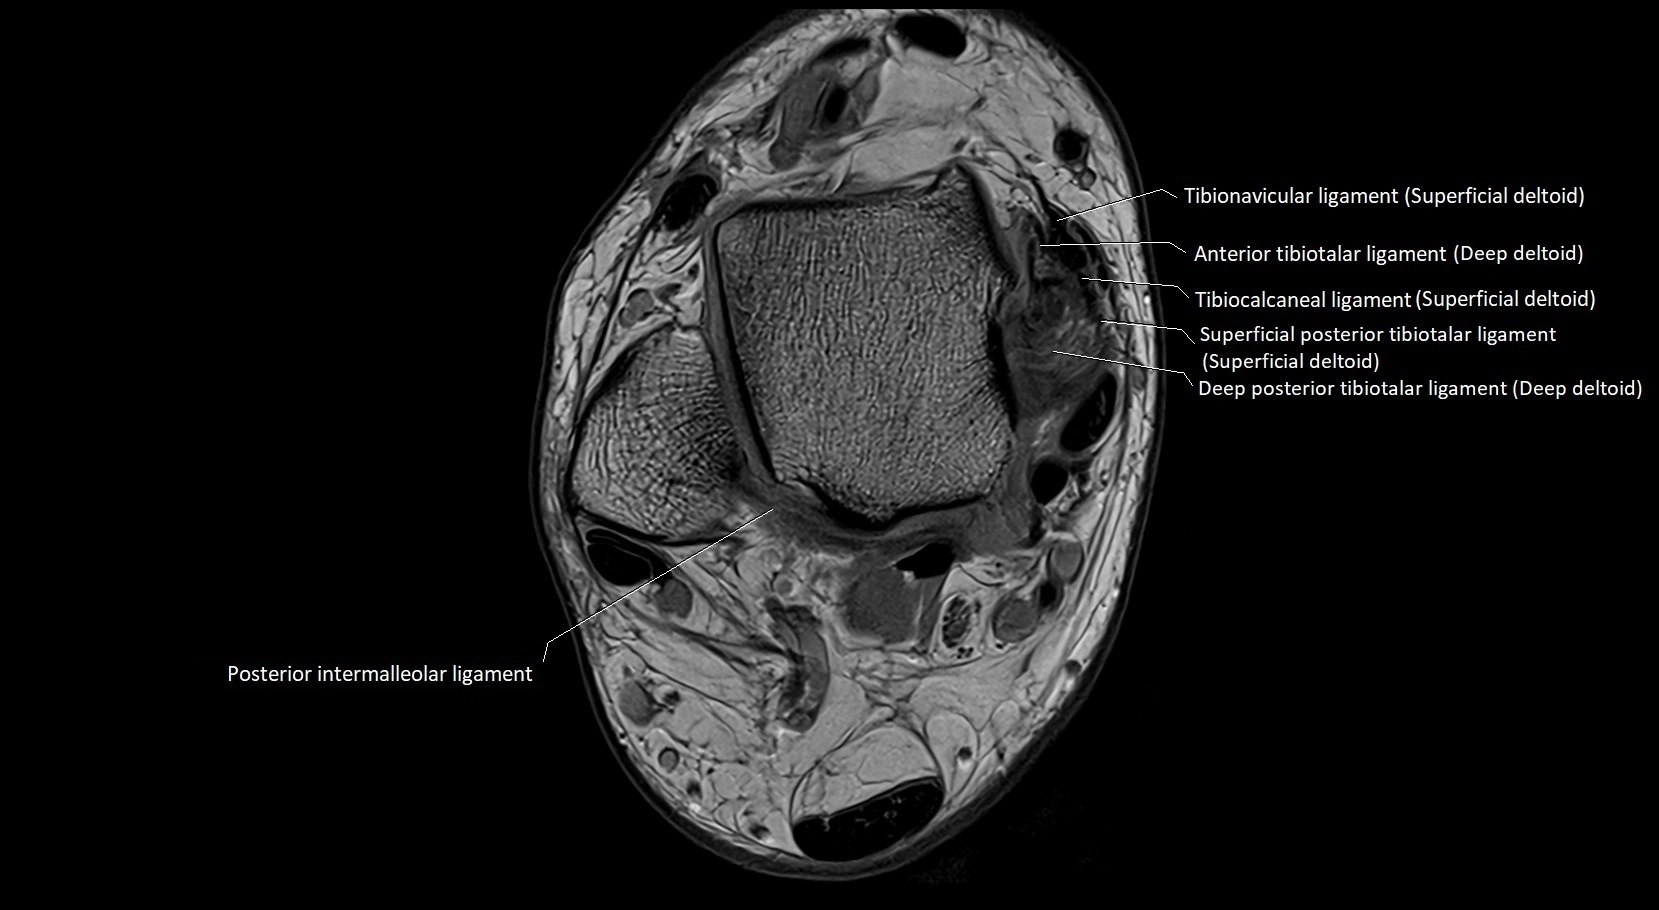

MRI image

image